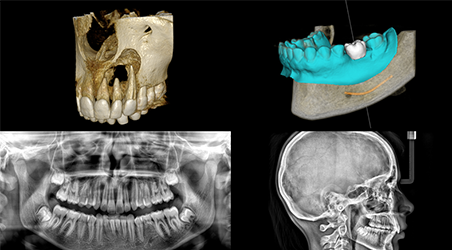

CS 8200 3D Access เป็นระบบ CBCT ที่ตอบโจทย์คลินิกทันตกรรมยุคใหม่ คุณภาพภาพที่ยอดเยี่ยม ฟังก์ชันครบ ใช้งานง่าย และรองรับการเชื่อมต่อเวิร์กโฟลว์ดิจิทัลอย่างเต็มรูปแบบ เหมาะสำหรับการใช้งานทั้งในงานรากเทียม ทันตกรรมจัดฟัน การรักษาราก และงานทั่วไปในคลินิก

1. ระบบ 4-in-1 ครบในเครื่องเดียว รองรับการถ่ายภาพ: พาโนรามา 2 มิติ, CBCT 3 มิติ, การถ่ายภาพกะโหลก (Cephalometric), การสแกนวัตถุ 3 มิติ

2. ความละเอียดสูง 75 ไมครอน ให้รายละเอียดภาพสูง เหมาะกับการวินิจฉัยในงานรักษารากฟันหรือวางแผนการปลูกฝังรากฟันเทียม

5. ขนาด Field of View (FOV) หลายระดับ รองรับตั้งแต่ 4×4 ซม. ถึง 10×10 ซม. ให้ความยืดหยุ่นในการเลือกภาพตามความเหมาะสมของการรักษา